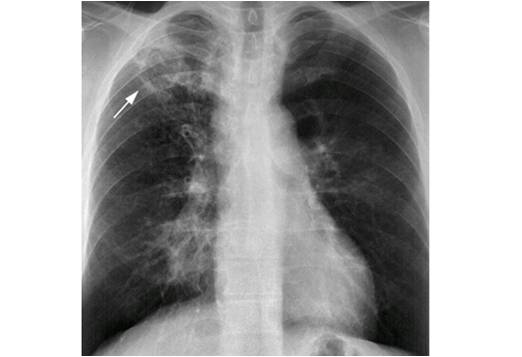

The following are examples of how Active TB may look on CXR:

Primary TB – LLL Infiltrate.

Mimics any pneumonia; occurs in debilitated pts, when Mtb first enters lung, and innate immune system unable to contain it.